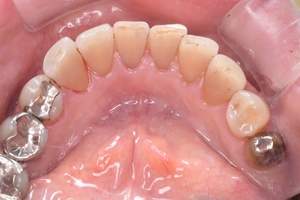

治療前

治療後

| 年齢 | 23歳・女性 |

|---|---|

| 主訴 | 着色取りたい |

| 治療内容 | エアフローで着色取り |

| 費用 | 5,500円(税込) (2024年07月現在) |

| 治療期間 | 1日 |

| リスク・副作用 | ナトリウムパウダーによるお口の不快感を伴うことがあります(うがいしていただくことで気にならない程度です)。 ケースにより完全に汚れを落としきれない場合があります。 歯ぐきの腫れや歯肉炎のある方は、ナトリウムパウダーがあたることにより、まれに痛みや出血をともなうことがあります。多くの場合、すぐに出血はおさまり、1~2日程度で歯ぐきは治癒していきます。 着色汚れはクリーニング後に再付着することがあります。定期的な受診をおすすめいたします。 |